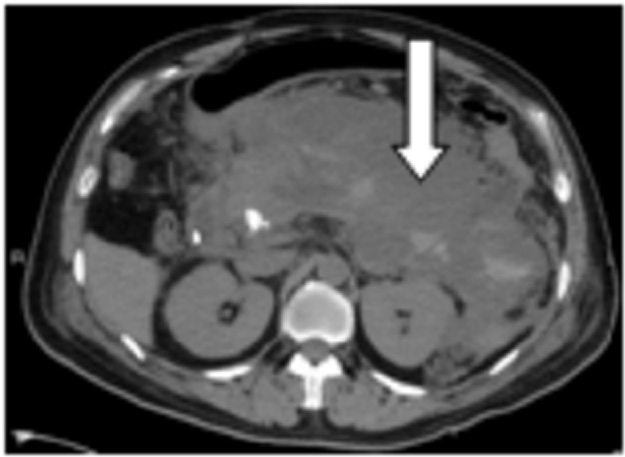

图 4 图中箭头提示胰头巨大血肿